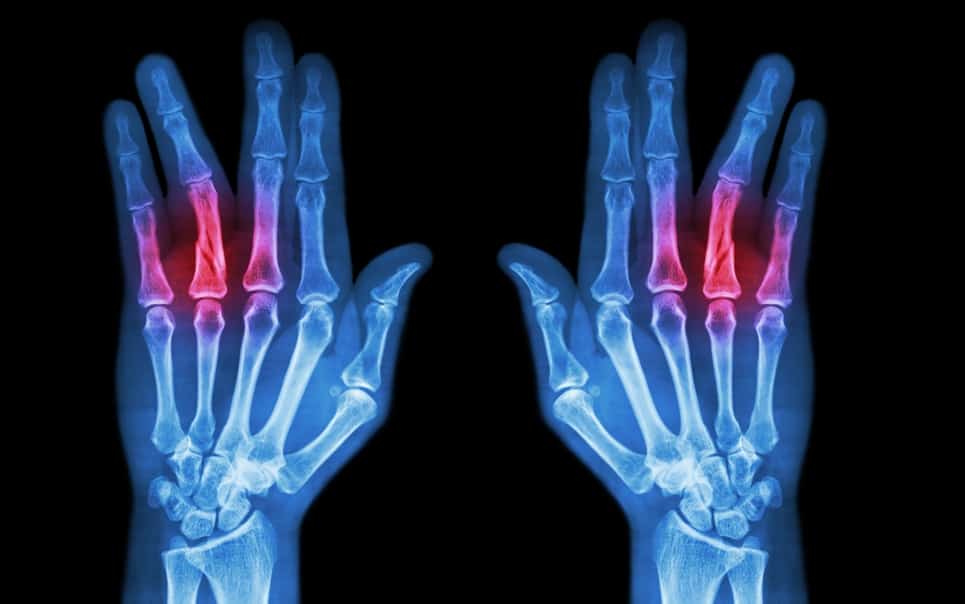

- 骨關節炎:磨損性關節炎。它還可能導致手指畸形。

醫師會檢查患者的手,包括力量測試,感覺和受傷部位影響的範圍。如果醫師懷疑您有骨折或傷口中有異物,例如玻璃或金屬,則可能需要進行X光檢查。不過X光不會顯示出所有的異物,也不會顯示肌腱或韌帶的傷害,例如:扭傷和拉傷。